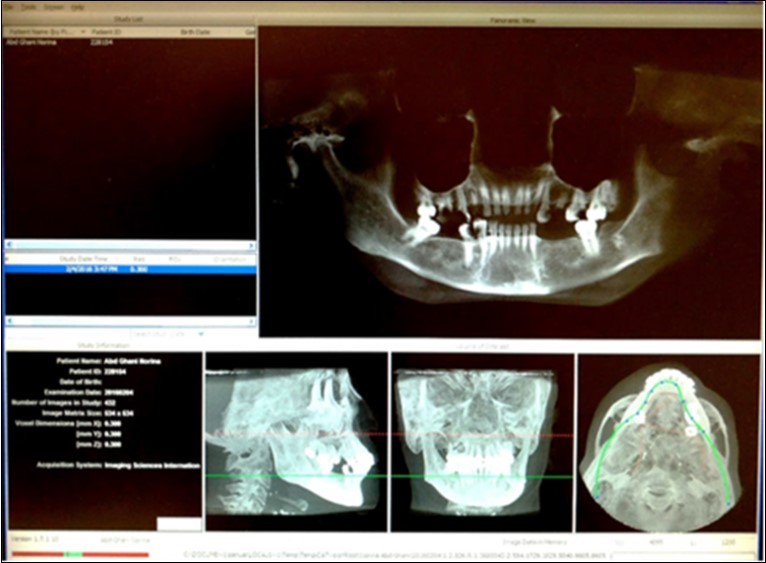

The maxillofacial CBCT examination was performed using i-CAT cone beam computed tomography (Imaging Sciences International, Hatfield, PA, USA) with tomography specifications of Tube Potential (Kv) 120, Current (mA) 5, Voxel Size (mm) 0.3 and scan time (s) 20-40 (Figure 1). Image analysis was performed using the i-CAT Vision Software, employing the multiplanar reconstruction (MPR) window in which axial, coronal and sagittal planes were visualized in 0.3mm intervals.

Figure 1.Screenshot of i-CAT Vision Program

Screenshot of i-CAT Vision Program